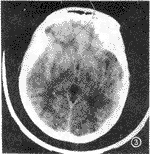

232例颅脑外伤CT随访检查中,61例发现颅内出现异常,其中60例CT复查时间为24h以内,1例为72h。61例中38例为原有的少量出血增多、血肿增大(图1,2)或出现新的血肿(图3,4),15例出现脑挫伤与脑内出血灶,8例出现对冲性脑血肿。

图3 伤后1hCT平扫。左颞部硬膜下少量出血,伴左侧环沟少量出血。

图4 同图3病例,24小时CT复查,左颞叶脑内血肿。